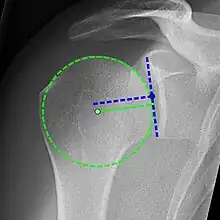

Xray

Projectional radiograph of normal glenohumeral position.[51]

High-riding humeral head in a rotator cuff tear.

X-ray projectional radiography cannot directly reveal tears of the rotator cuff, a 'soft tissue', and consequently, normal X-rays cannot exclude a damaged cuff. However, indirect evidence of pathology may be seen in instances where one or more of the tendons has undergone degenerative calcification (calcific tendinitis). The humeral head may migrate upward (high-riding humeral head) secondary to tears of the infraspinatus, or combined tears of the supraspinatus and infraspinatus.[51] The migration can be measured by the distance between:

• A line crossing the center of a line between the superior and inferior rims of the glenoid articular surface (blue in image).

• The center of a "best-fit" circle positioned over the humeral articular surface (green in image)

Normally, the former is positioned inferiorly to the latter, and a reversal therefore indicates a rotator cuff tear.[51] Prolonged contact between a high-riding humeral head and the acromion above it may lead to X-ray findings of wear on the humeral head and acromion; secondary degenerative arthritis of the glenohumeral joint (the ball and socket joint of the shoulder), called cuff arthropathy, may follow.[50] Incidental X-ray findings of bone spurs at the adjacent acromioclavicular joint may show a bone spur growing from the outer edge of the clavicle downward toward the rotator cuff. Spurs may also be seen on the underside of the acromion, once thought to cause direct fraying of the rotator cuff from contact friction, a concept currently regarded as controversial.